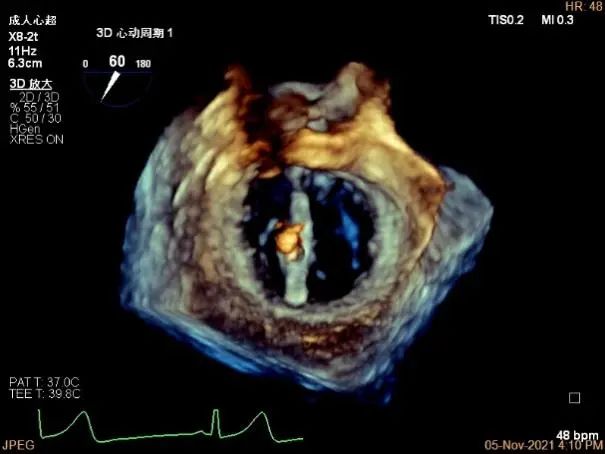

3D MV View:A2/A1区脱垂

3D-color MV view:血流主要来源于A2区,少部分来源于A1区

3D视图下观察二尖瓣双孔形态

3D-color:残余少量返流